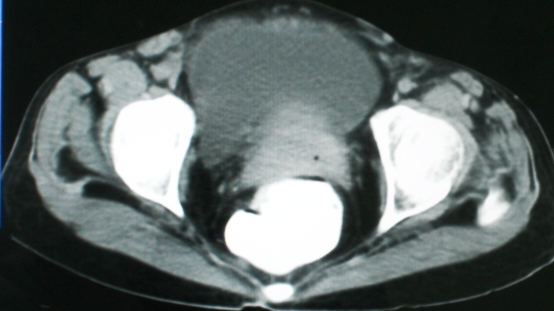

以下是引用zsl6918在2008-11-4 19:14:00的发言:[br]多发转移性改变,子宫改变不除外为原发灶